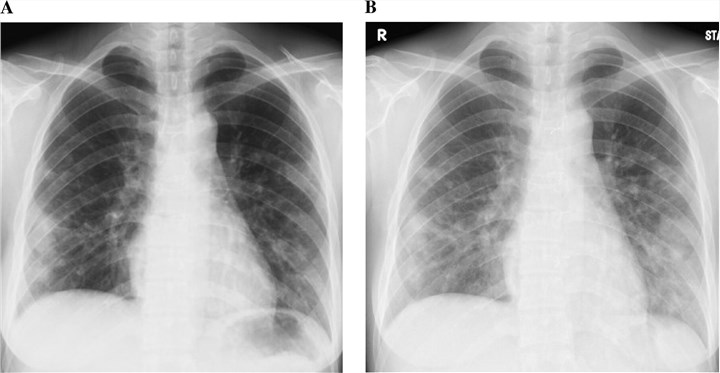

Chest X-ray

It is used to check for damage to your lungs and help confirm the diagnosis.

Fig. 1 Chest radiography shows enlargement of the lung nodules in coccidioidomycosis.1